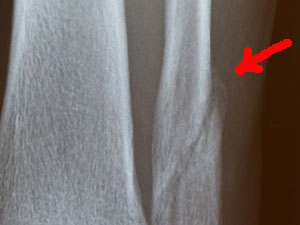

| わずかに斜めから撮ったレントゲン。左が8週間前、右が今日の写真。 「ほらね、こっちから見ると影が薄くなっているのが分かるでしょう。大分治ってきてますね。」とのこと。 |

アップにすると、ここが盛り上がってきてるでしょう。これが、新しい骨ができているところです。 もう松葉杖は無しでもいいですよ。装具はまだしといて下さいね。じゃあ、次は1ヶ月後に来て下さい。 と言う事で、今日から普通に歩いても良い事になった。有り難し。 |